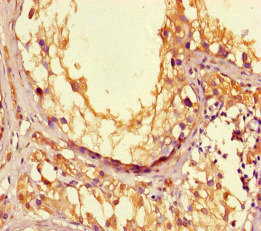

Immunohistochemistry of paraffin-embedded human testis tissue using PACO46518 at dilution of 1:100.